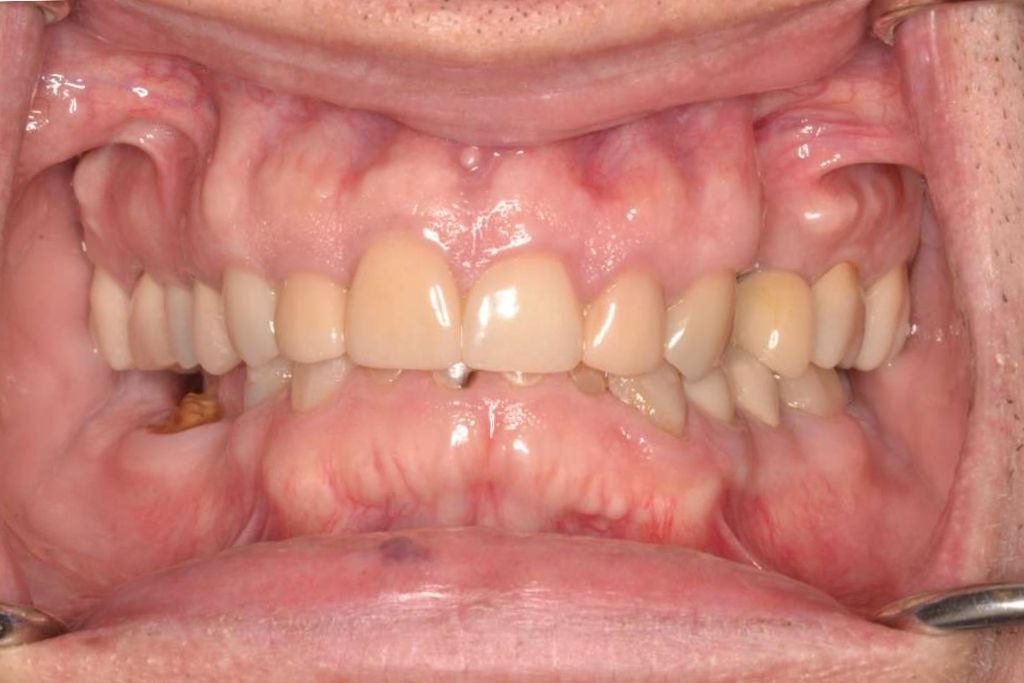

Before, After, and Beyond: Real Benefits of All on X Dental Implants

The results speak for themselves. Patients who once struggled with missing teeth, loose dentures, or limited diets often experience dramatic improvements after All on X dental implant treatment. It’s more than just a cosmetic upgrade — it’s a full-spectrum transformation.